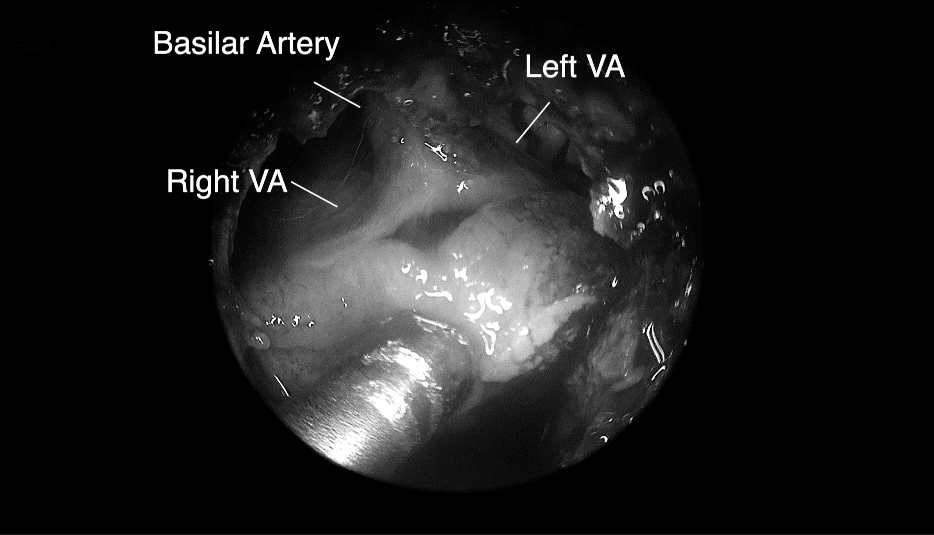

將腫瘤分離出來(lái)——Basilar Artery,基底動(dòng)脈;Left VA,左側(cè)椎動(dòng)脈; Right VA,右側(cè)椎動(dòng)脈;